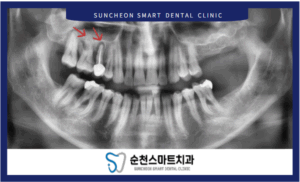

치료를 위한 전 사진

24.01.03

처음 내원하셨을 때의 모습입니다.

먼저 눈에 띄는 것은

왼쪽(사진에서 오른쪽) 위에는 어금니 2개 상실하셨고,

왼쪽 아래는 어금니 1개를 상실한 상태셨는데요.

치아의 맞물림인 교합이

잘 되지  않으며,

저작 시 힘을 받지 못하는

상태이시기 때문에

당연히 주로 오른쪽을 식사를 하실 수 밖에

없으셨으리라 생각됩니다.

사진에 표시된

오른쪽(사진에서 왼쪽) 위 작은 어금니와 큰 어금니는

치아 뿌리 주변이 검게 된 것을 볼 수 있는데요.

이는

치조골이 녹아서

치아를 잡아주지 못한 상태였습니다.

흔들림이 심해서

살리기 어려운 것으로

판단되었습니다.